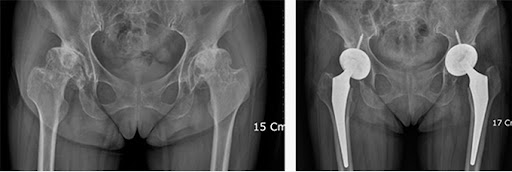

고관절 수술은 많은 사람들에게 필요한 복잡한 수술입니다. 나이가 들면서 또는 외상으로 인해 고관절의 기능이 떨어지면, 수술이 불가피해질 수 있습니다. 하지만 이러한 수술이 끝난 뒤에도 많은 이들이 어떤 과정을 거쳐 회복할 수 있을지에 대한 걱정이 많습니다. 이 블로그 글에서는 고관절 수술 후 회복기간과 단계별 재활 과정에 대해 상세히 알아보겠습니다. 정확한 정보를 통해 여러분의 회복 과정이 더욱 원활해지길 바랍니다.

고관절 수술 후 회복기간은 많은 요인에 따라 달라질 수 있습니다. 환자의 나이, 건강 상태, 수술 유형 등이 이에 포함됩니다. 고관절 수술의 전형적인 기간은 수술 후 6주에서 6개월까지 다양할 수 있습니다. 이 시간 동안 몸은 점진적으로 회복되며, 환자는 일상생활로 복귀할 수 있게 됩니다.